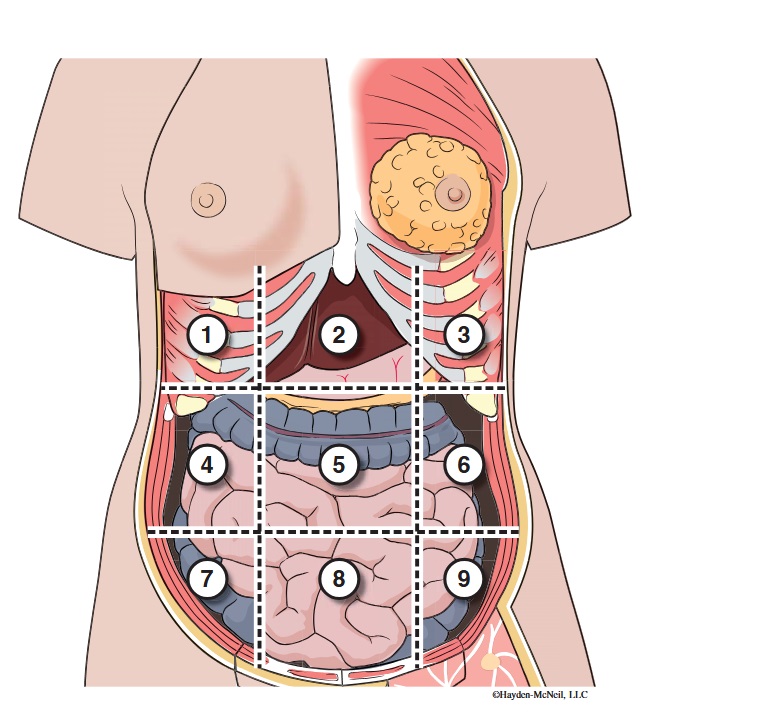

What abdominal region is labeled #1?

right hypochondriac

What abdominal region is labeled #2?

epigastric

What abdominal region is labeled #3?

left hypochondriac

What abdominal region is labeled #4?

right lumbar

What abdominal region is labeled #5?

umbilical

What abdominal region is labeled #6?

left lumbar

What abdominal region is labeled #7?

right iliac/ inguinal

What abdominal region is labeled #8?

hypogastric

What abdominal region is labeled #9?

left illiac/ inguinal

What organs are apart of the right hypochrondriac region?

right lobe of liver, gallbladder, right adrenal gland

What organs are apart of the epigastric region?

pyloric end of stomach, duodenum, pancreas

What organs are apart of the left hypochondriac region?

stomach, spleen, left adrenal gland

What organs are apart of the right lumbar region?

ascending colon, right kidney, portion of small intestine

What organs are apart of the umbilical region?

omentum, mesentery, small intestine

What organs are apart of the left lumbar region?

descending colon, left kidney, portion of the small intestine

What organs are apart of the right iliac/ inguinal region?

cecum of large intestines, appendix, right ovary

What organs are apart of the hypogastric region?

ileum, bladder, uterus

What organs are apart of the left iliac/ inguinal region?

sigmoid colon, left ureter, left ovary